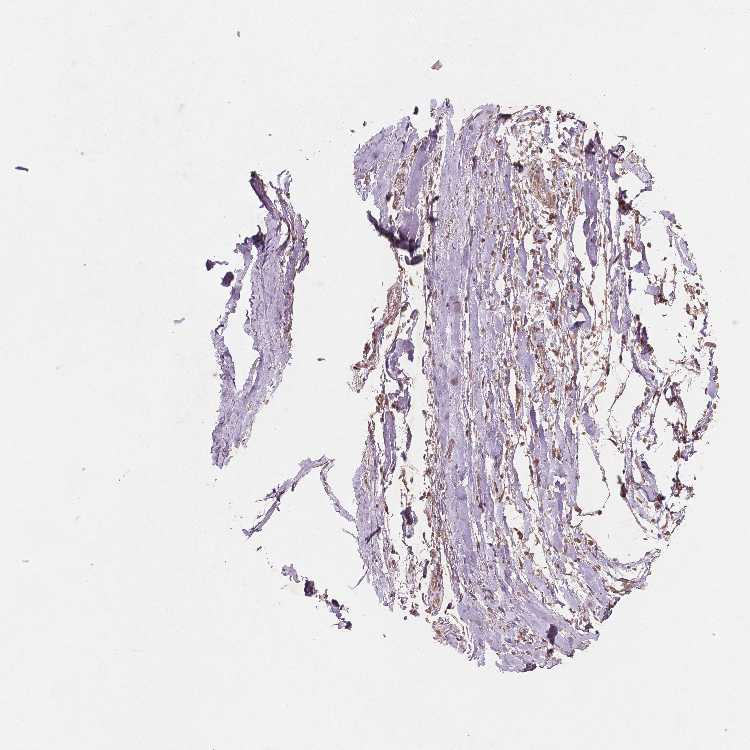

SOFT TISSUE 2 - Antibody stainingi

Antibody staining in the annotated cell types in the current human tissue is reported as not detected, low, medium, or high, based on conventional immunohistochemistry profiling in selected tissues. This score is based on the combination of the staining intensity and fraction of stained cells.

Each image is clickable and will lead to virtual microscopy that enables deeper exploration of all samples and also displays staining intensity scores, fraction scores and subcellular localization as well as patient and tissue information for each sample.

Antibody HPA067203Antibody CAB025507Antibody CAB073546

Chondrocytes -Not detected-

Fibroblasts Not detectedMediumMedium

Peripheral nerve Not detectedMediumNot detected